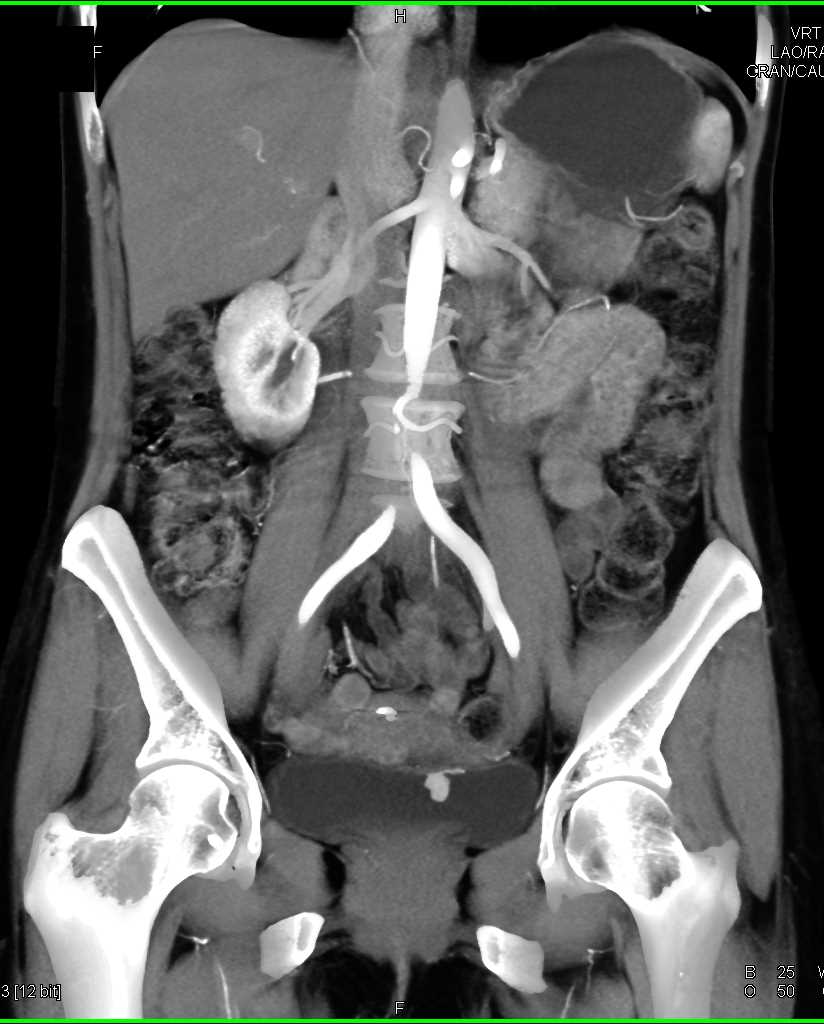

Bladder Cancer with Active Bleed